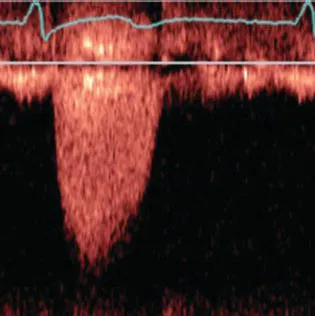

- CW/PW Doppler: the representation of flow velocities as plotted with time on the x axis and velocity on the y axis (Figure 1.7).